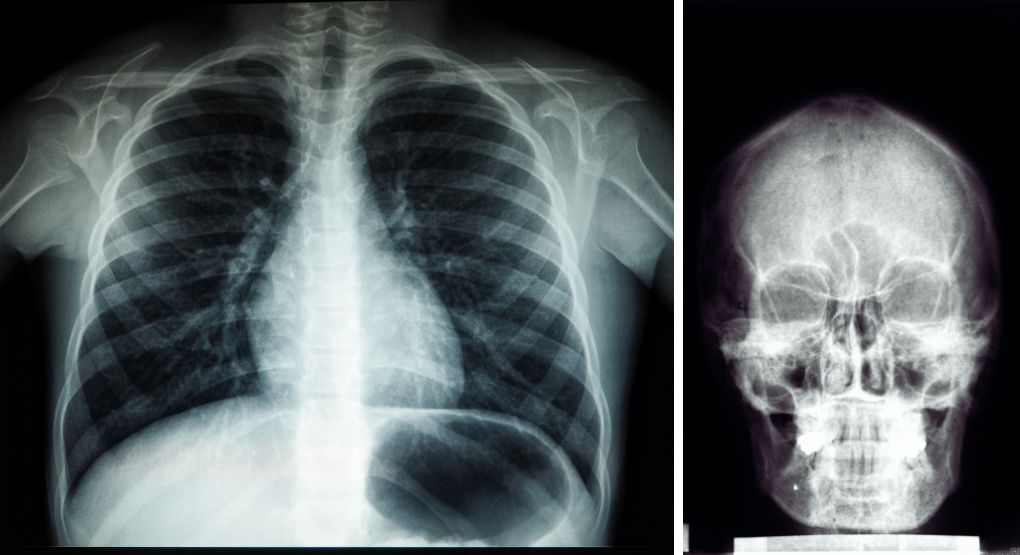

Radiografía: una herramienta diagnostica para detectar problemas de salud

La lectura de una radiografía combina la imagen con los síntomas clínicos del paciente. Publicado en Repretel .